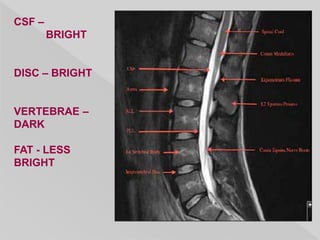

CSF –

BRIGHT

DISC – BRIGHT

VERTEBRAE –

DARK

FAT - LESS

CSF – BRIGHT DISC –BRIGHT VERTEBRAE – DARK FAT - LESS BRIGHT